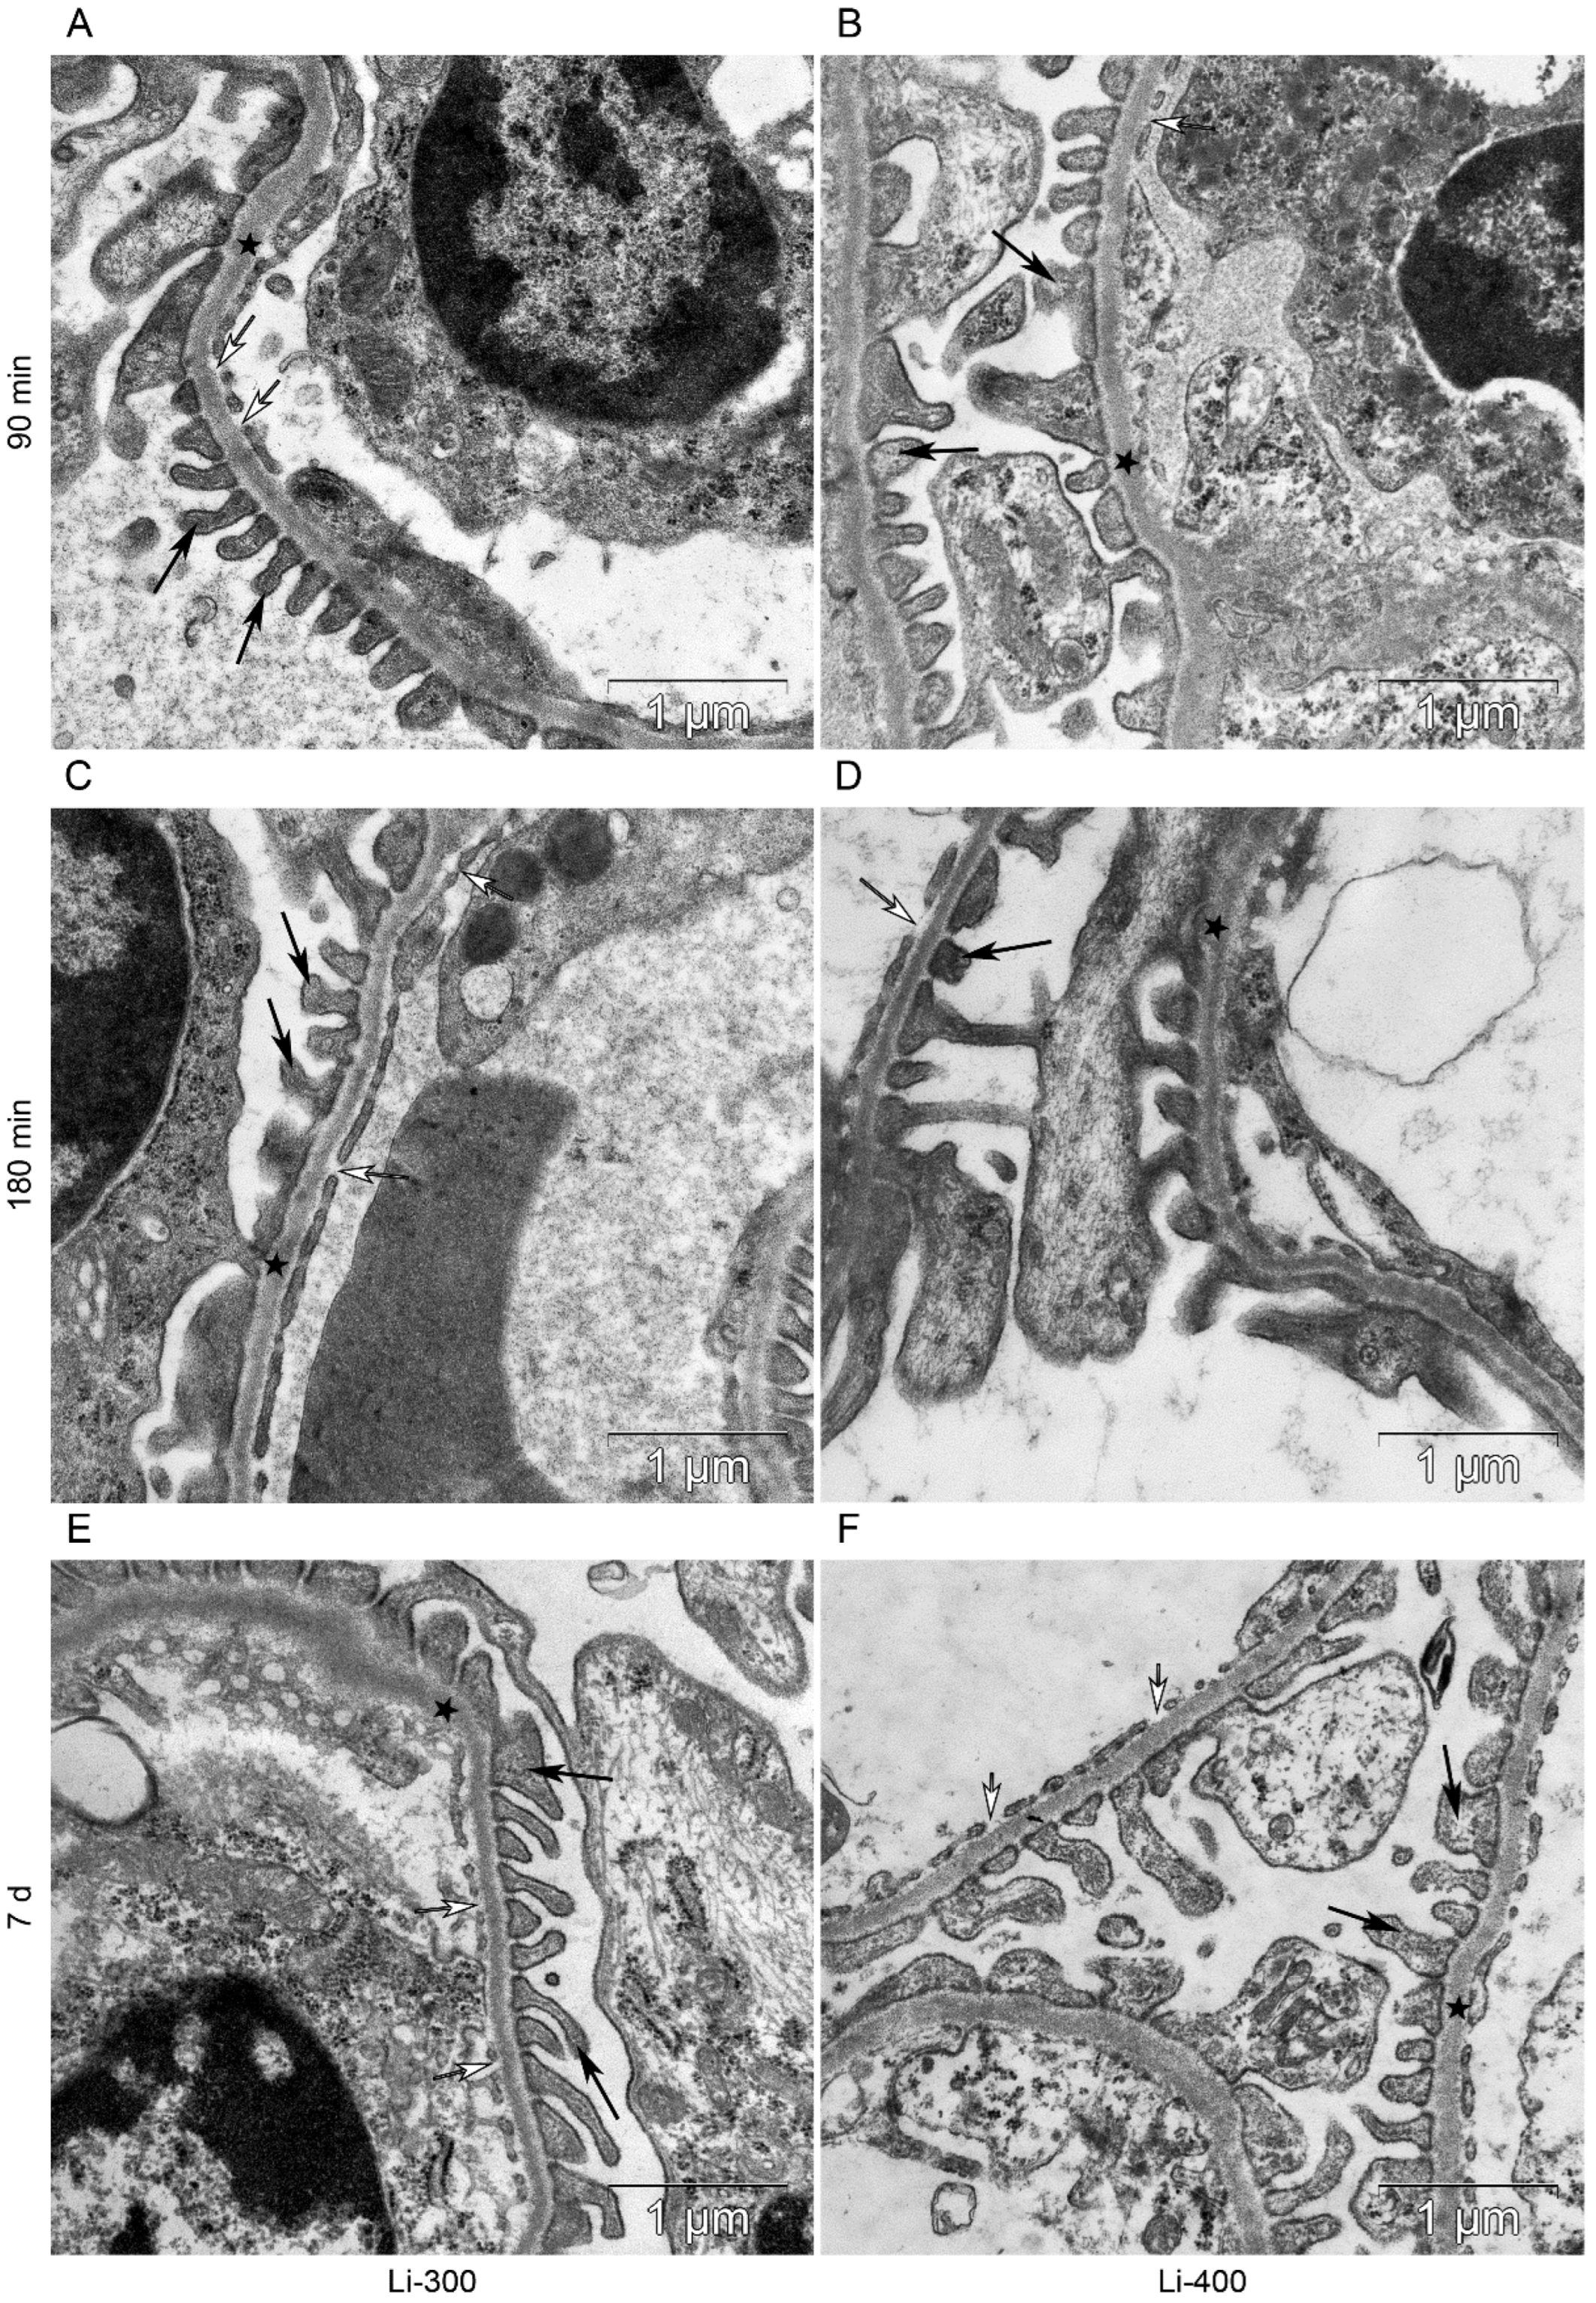

3.4. Ultrastructural Organization of the Kidney Filtration Barrier and Proximal Tubules

| Group/ Parameters | GBM, Thickness, μm | PFP, Width μm | PFP/ 2 µm GBM | BMPT, Thickness, μm | Fenestrae/ 2 µm GBM | Slit Diaphragm, Width, nm |

|---|---|---|---|---|---|---|

| Control | 0.11 ± 0.01 | 0.3 ± 0.2 | 6 ± 2 | 0.14 ± 0.03 | 3.6 ± 1.7 | 34.6 ± 9.8 |

| Li-300, 15 min | 0.11 ± 0.01 | 0.3 ± 0.1 | 5.0 ± 1.6 | 0.13 ± 0.02 | 3.8 ± 0.8 | 34.8 ± 6.9 |

| Li-300, 30 min | 0.12 ± 0.01 | 0.3 ± 0.1 | 5.8 ± 1.1 | 0.12 ± 0.01 | 4.4 ± 1.5 | 31.1 ± 7.5 |

| Li-300, 90 min | 0.14 ± 0.02 | 0.3 ± 0.2 | 5.6 ± 2.7 | 0.13 ± 0.03 | 4.2 ± 1.7 | 34.4 ± 11.5 |

| Li-300, 180 min | 0.12 ± 0.02 | 0.3 ± 0.2 | 5.4 ± 0.8 | 0.13 ± 0.02 | 3.2 ± 1.3 | 32.4 ± 8.7 |

| Li-300, 7 d | 0.11 ± 0.01 | 0.2 ± 0.1 | 6.6 ± 2.0 | 0.12 ± 0.02 | 4.8 ± 1.3 | 35.5 ± 7.1 |

| Li-400, 15 min | 0.12 ± 0.01 | 0.2 ± 0.1 | 7.0 ± 0.8 | 0.12 ± 0.01 | 3.8 ± 1.1 | 27.1 ± 5.8 |

| Li-400, 30 min | 0.11 ± 0.02 | 0.2 ± 0.1 | 6.5 ± 1.3 | 0.12 ± 0.01 | 4.3 ± 0.5 | 31.1 ± 11.3 |

| Li-400, 90 min | 0.12 ± 0.02 | 0.3 ± 0.2 | 6.4 ± 1.9 | 0.13 ± 0.02 | 3.4 ± 1.6 | 31.1 ± 7.5 |

| Li-400, 180 min | 0.13 ± 0.02 | 0.3 ± 0.2 | 5.4 ± 2.1 | 0.12 ± 0.02 | 3.4 ± 1.5 | 29.1 ± 6.9 |

| Li-400, 7 d | 0.13 ± 0.02 | 0.2 ± 0.1 | 7 ± 1.5 | 0.13 ± 0.01 | 5 ± 1 | 35.7 ± 9.8 |